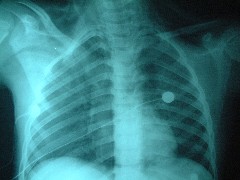

骨盤内の弾丸に関しては、側面像で仙骨内にとどまっていることが確認され、フォローアップということになった

(写真右:仙骨内に弾丸が見える)。